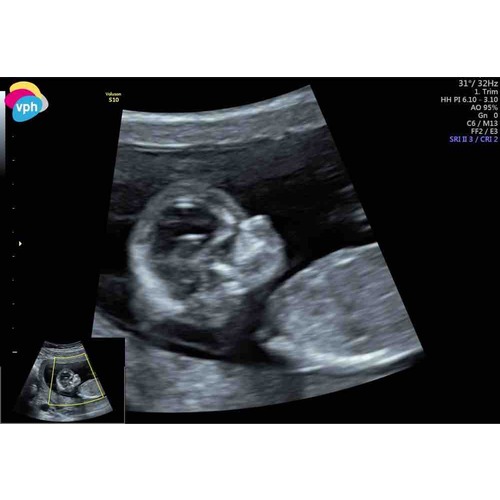

Iemand enig idee wat het wordt? Is een 12 weken echo.

Ik denk een meisje

Ben net geweest… its a boy🥺💙💙💙